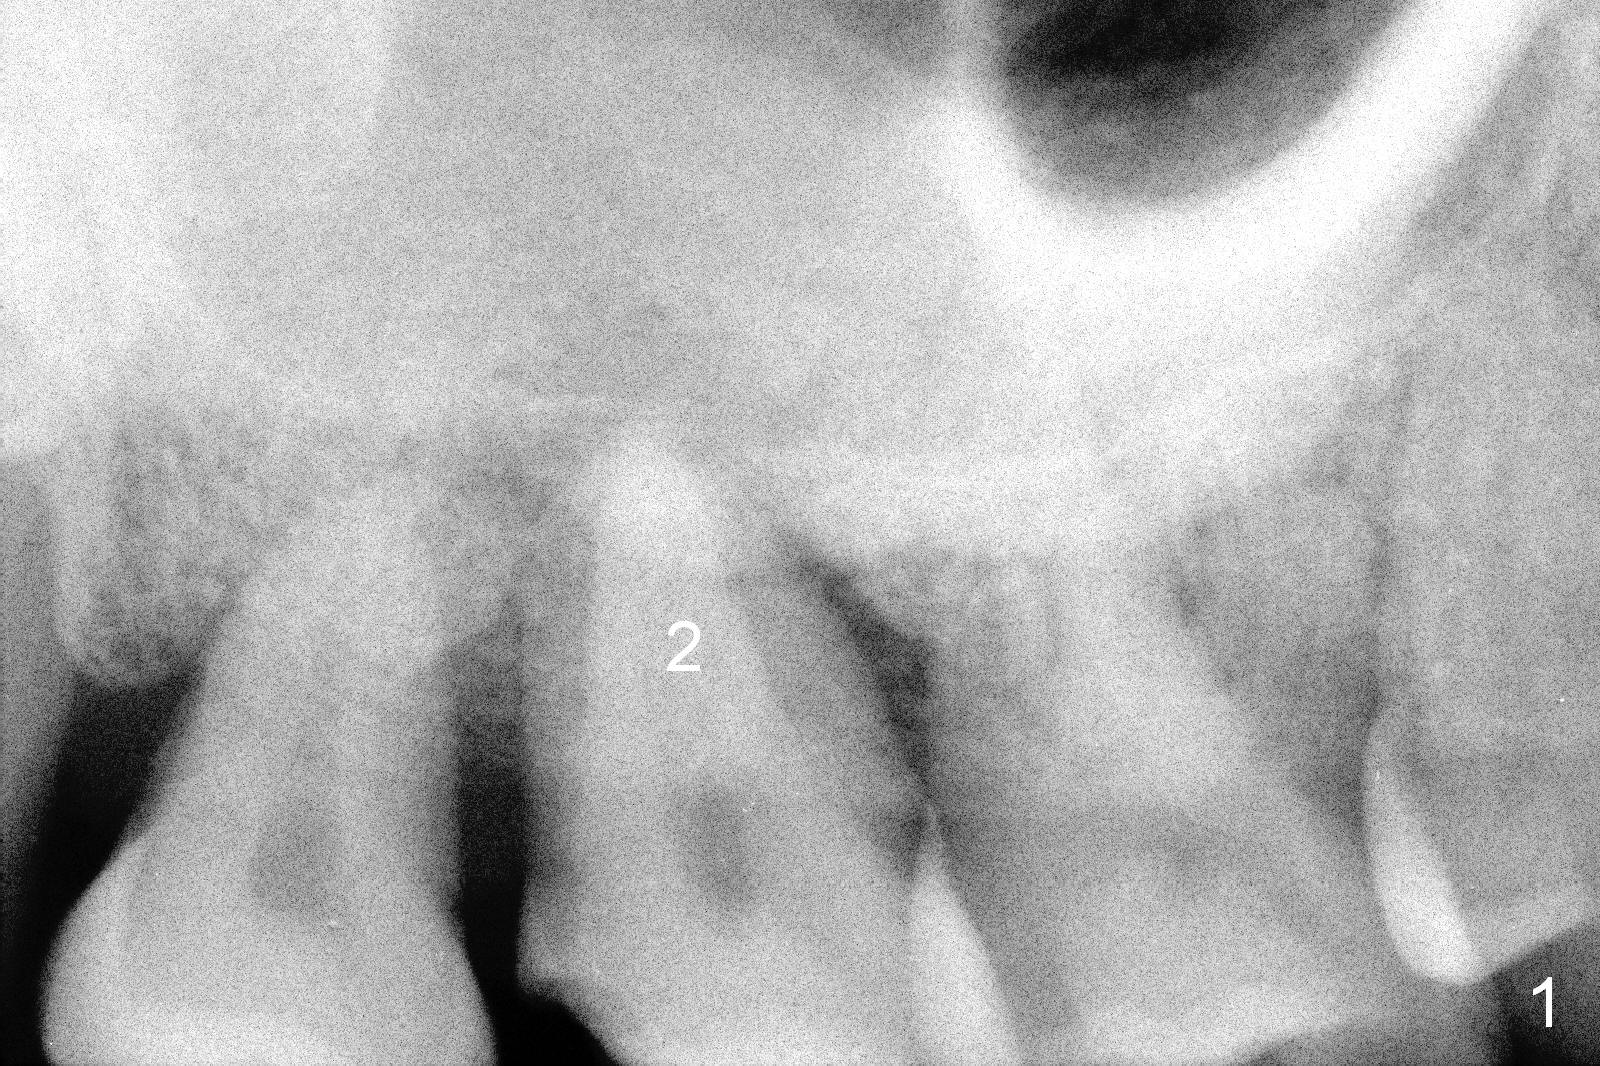

There is a tendency to drift osteotomy distally at the upper 2nd molar area when the 3rd molar is missing. Without a surgical stent, an implant spacer should be used constantly from the beginning (pilot drill) to the end (implant placement, Fig.3) for the site of #2 of the 47-year-old man (Fig.2). The tooth was extracted because of periodontitis and bruxism (Fig.1 (taken 5 years earlier)). Please measure the diameter of the handle of every instrument, including drill, expander and implant driver in advance (Fig.3 red lines). The center of the handle should be 5 mm from the distal surface of the 1st molar. If the diameter of the handle is 2 mm, the implant spacer is set to be 4 mm (Fig.3). For convenience of insertion (the edge of the spacer is wider than the center), use the 3.5 mm one. Take PA as early as possible and change position with a Lindamann bur accordingly. Prepare Magic Sinus Kit and separate IBS implant driver (in a pouch, not from a cassette).